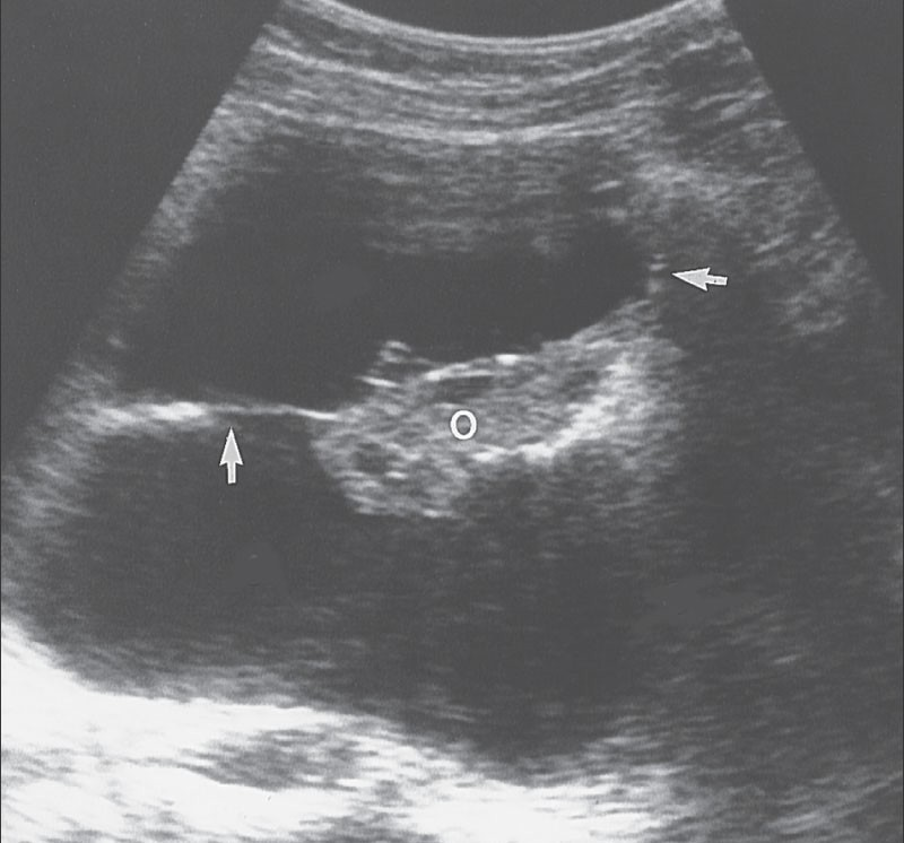

Dermoid Tumor

-dermoid mesh

Dermoid Cyst

-tip of the iceburg